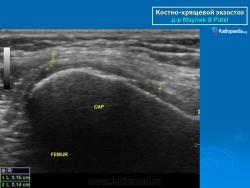

Локализация остеохондромы: частота поражения отдельных костей различна; нижний коней бедренной кости, верхние отделы плечевой и большеберцовой костей поражаются более чем у половины больных. На всем протяжении остеохондрома покрыта надкостницей. Она может быть обнаружена и в других костях, за исключением костей лицевого черепа. Все же поражение костей позвоночника, кистей рук и стоп встречается редко. При рентгенологическом исследовании видна типичная картина узкого или широкого выроста вблизи эпифизарной части пораженной кости. Обычно плотность узла неоднородная, имеются многочисленные плотные участки, соответствующие обызвествленным хрящевым долькам. Хрящевая «шапочка» большей частью не определяется, поскольку хрящ остается необызвествленным. Она может быть выявлена только при магнитно-резонансной томографии.

Костно-хрящевые экзостозы (остеохондрома).

Костно-хрящевые экзостозы